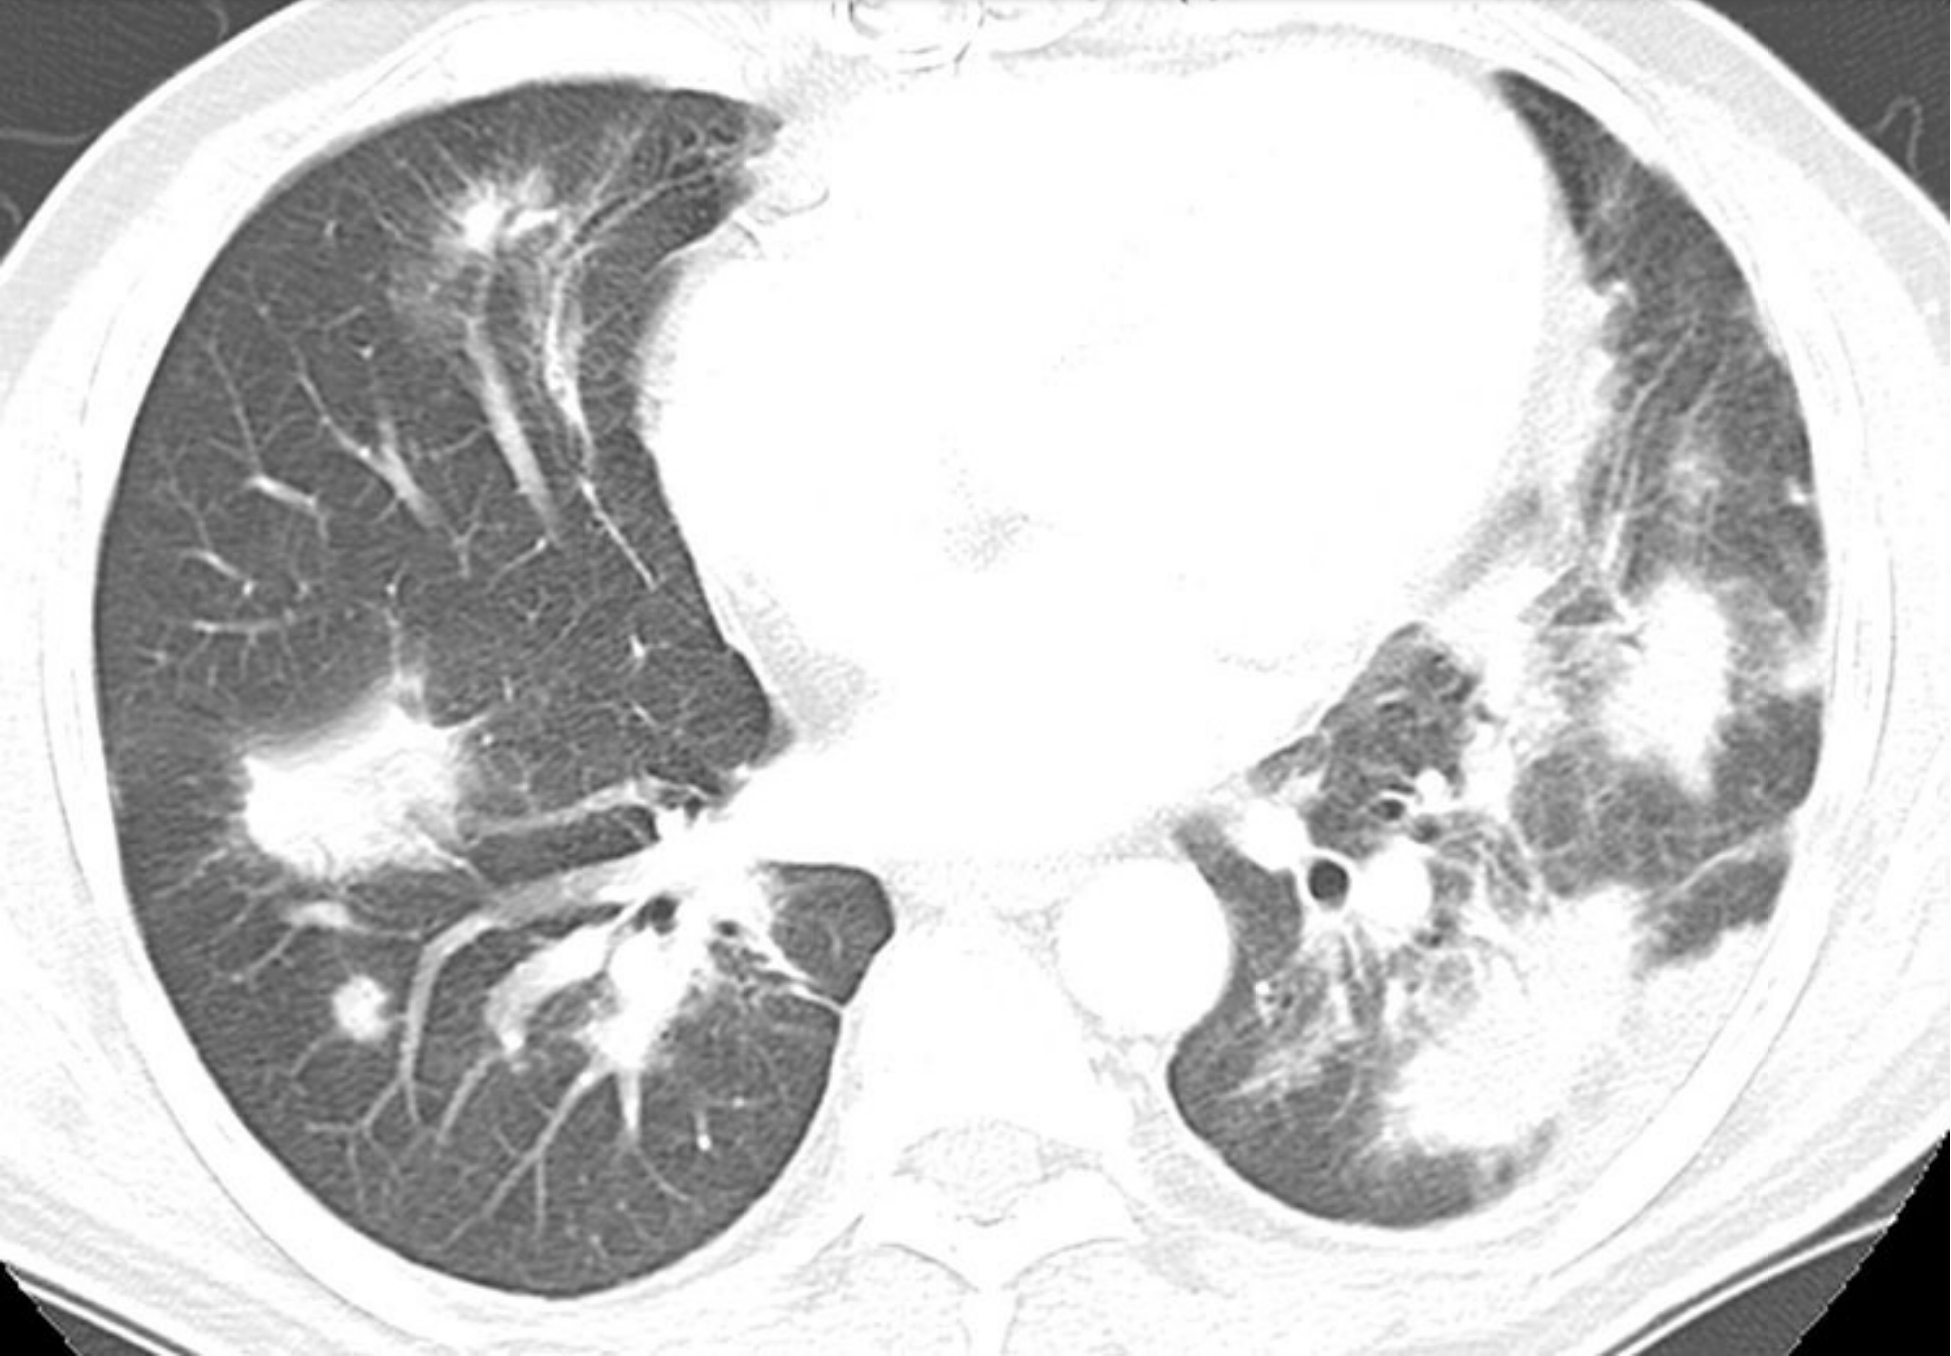

37748ee2c35e58319101755ab1db6efa.jpg

普通型间质性肺炎的分布。

经主动脉弓(A)、气管隆嵴(B)及肺基底(C)平面的HRCT显示胸膜下和肺基底分布为主的蜂窝征。冠状位(D)和冠状位最小强度投影(MIP)重组(E)均明确显示了位于肺基底的病变。